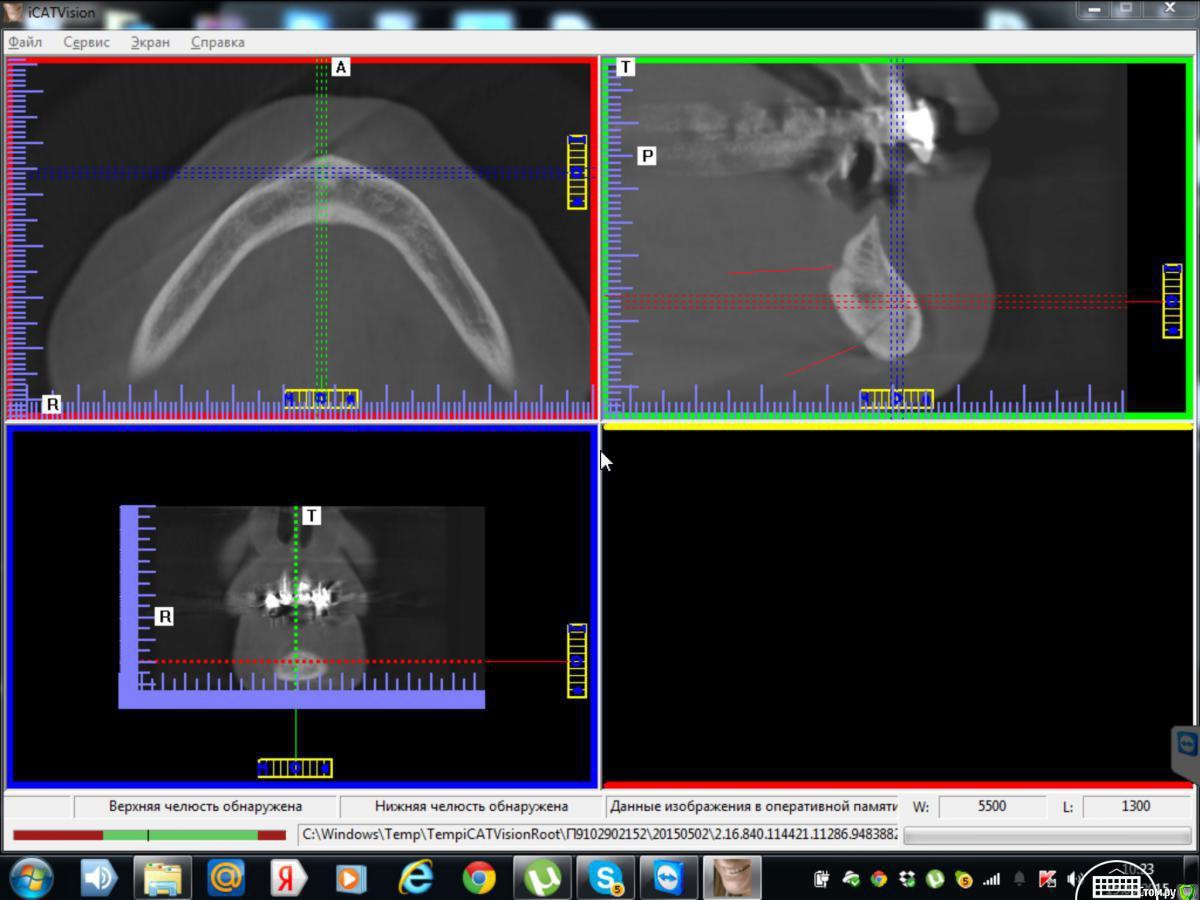

kriokov Опубликовано 7 мая, 2015 Поделиться Опубликовано 7 мая, 2015 они в Вашем случае входят язычно ниже диафрагмы, и похоже на канал во фронтальной части. Посмотрите на аксиальном срезе может получше видно будет Ссылка на комментарий

syrovovec Опубликовано 15 мая, 2015 Поделиться Опубликовано 15 мая, 2015 они в Вашем случае входят язычно ниже диафрагмы, и похоже на канал во фронтальной части. Посмотрите на аксиальном срезе может получше видно будетКак-то так? Не видно канала вроде? Ссылка на комментарий

kriokov Опубликовано 15 мая, 2015 Поделиться Опубликовано 15 мая, 2015 не критично, все прям как в книгах. Один сосуд низко, второй повыше. Но оба в центральной зоне, Вы же болт по центру симфиза не будите крутить. Канала нет, справа кость не очень плотная помоему. 1 Ссылка на комментарий